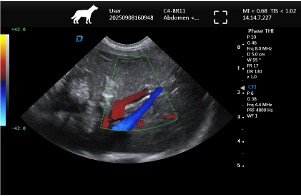

| Imaging Quality | Clear 2D, stable grayscale, optional Color Doppler for abdominal, cardiac, reproductive exams | Ensure system covers most frequent clinical exams |

Common Clinical Applications

▸ Basic cardiac screening